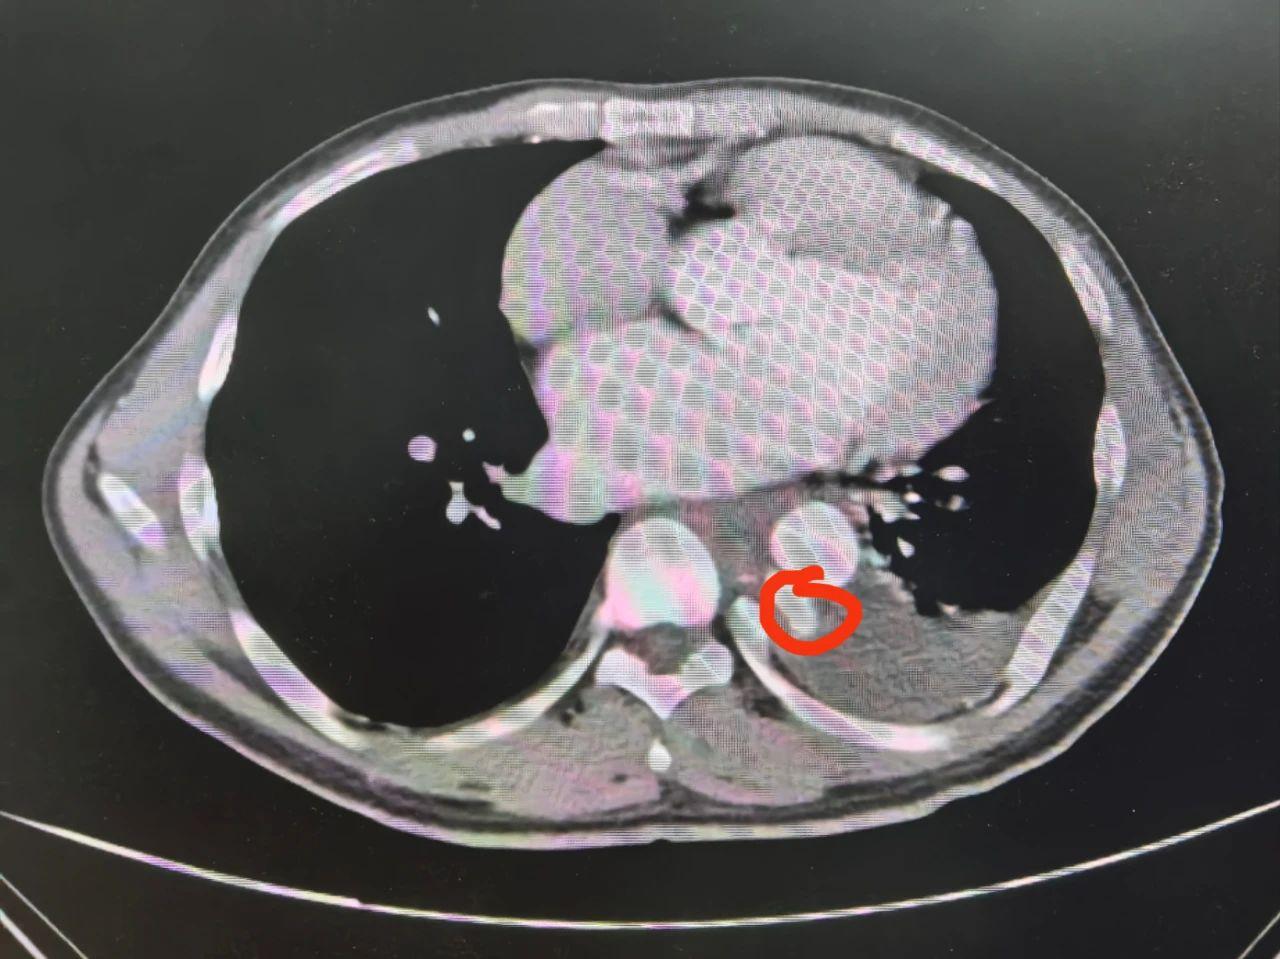

患者转入贵医大二院心胸外科后,医生对首次引出的600毫升血性积液产生怀疑,随即邀请介入科会诊。检查期间,患者胸腔再次引流出800毫升积液,进一步检查后,结果显示:胸主动脉破裂并伴假性动脉瘤形成,病情十分危急。介入科建议立即手术,通过“胸主动脉覆膜支架腔内隔绝术”稳定破裂血管区域,恢复正常血流。

血性胸腔积液